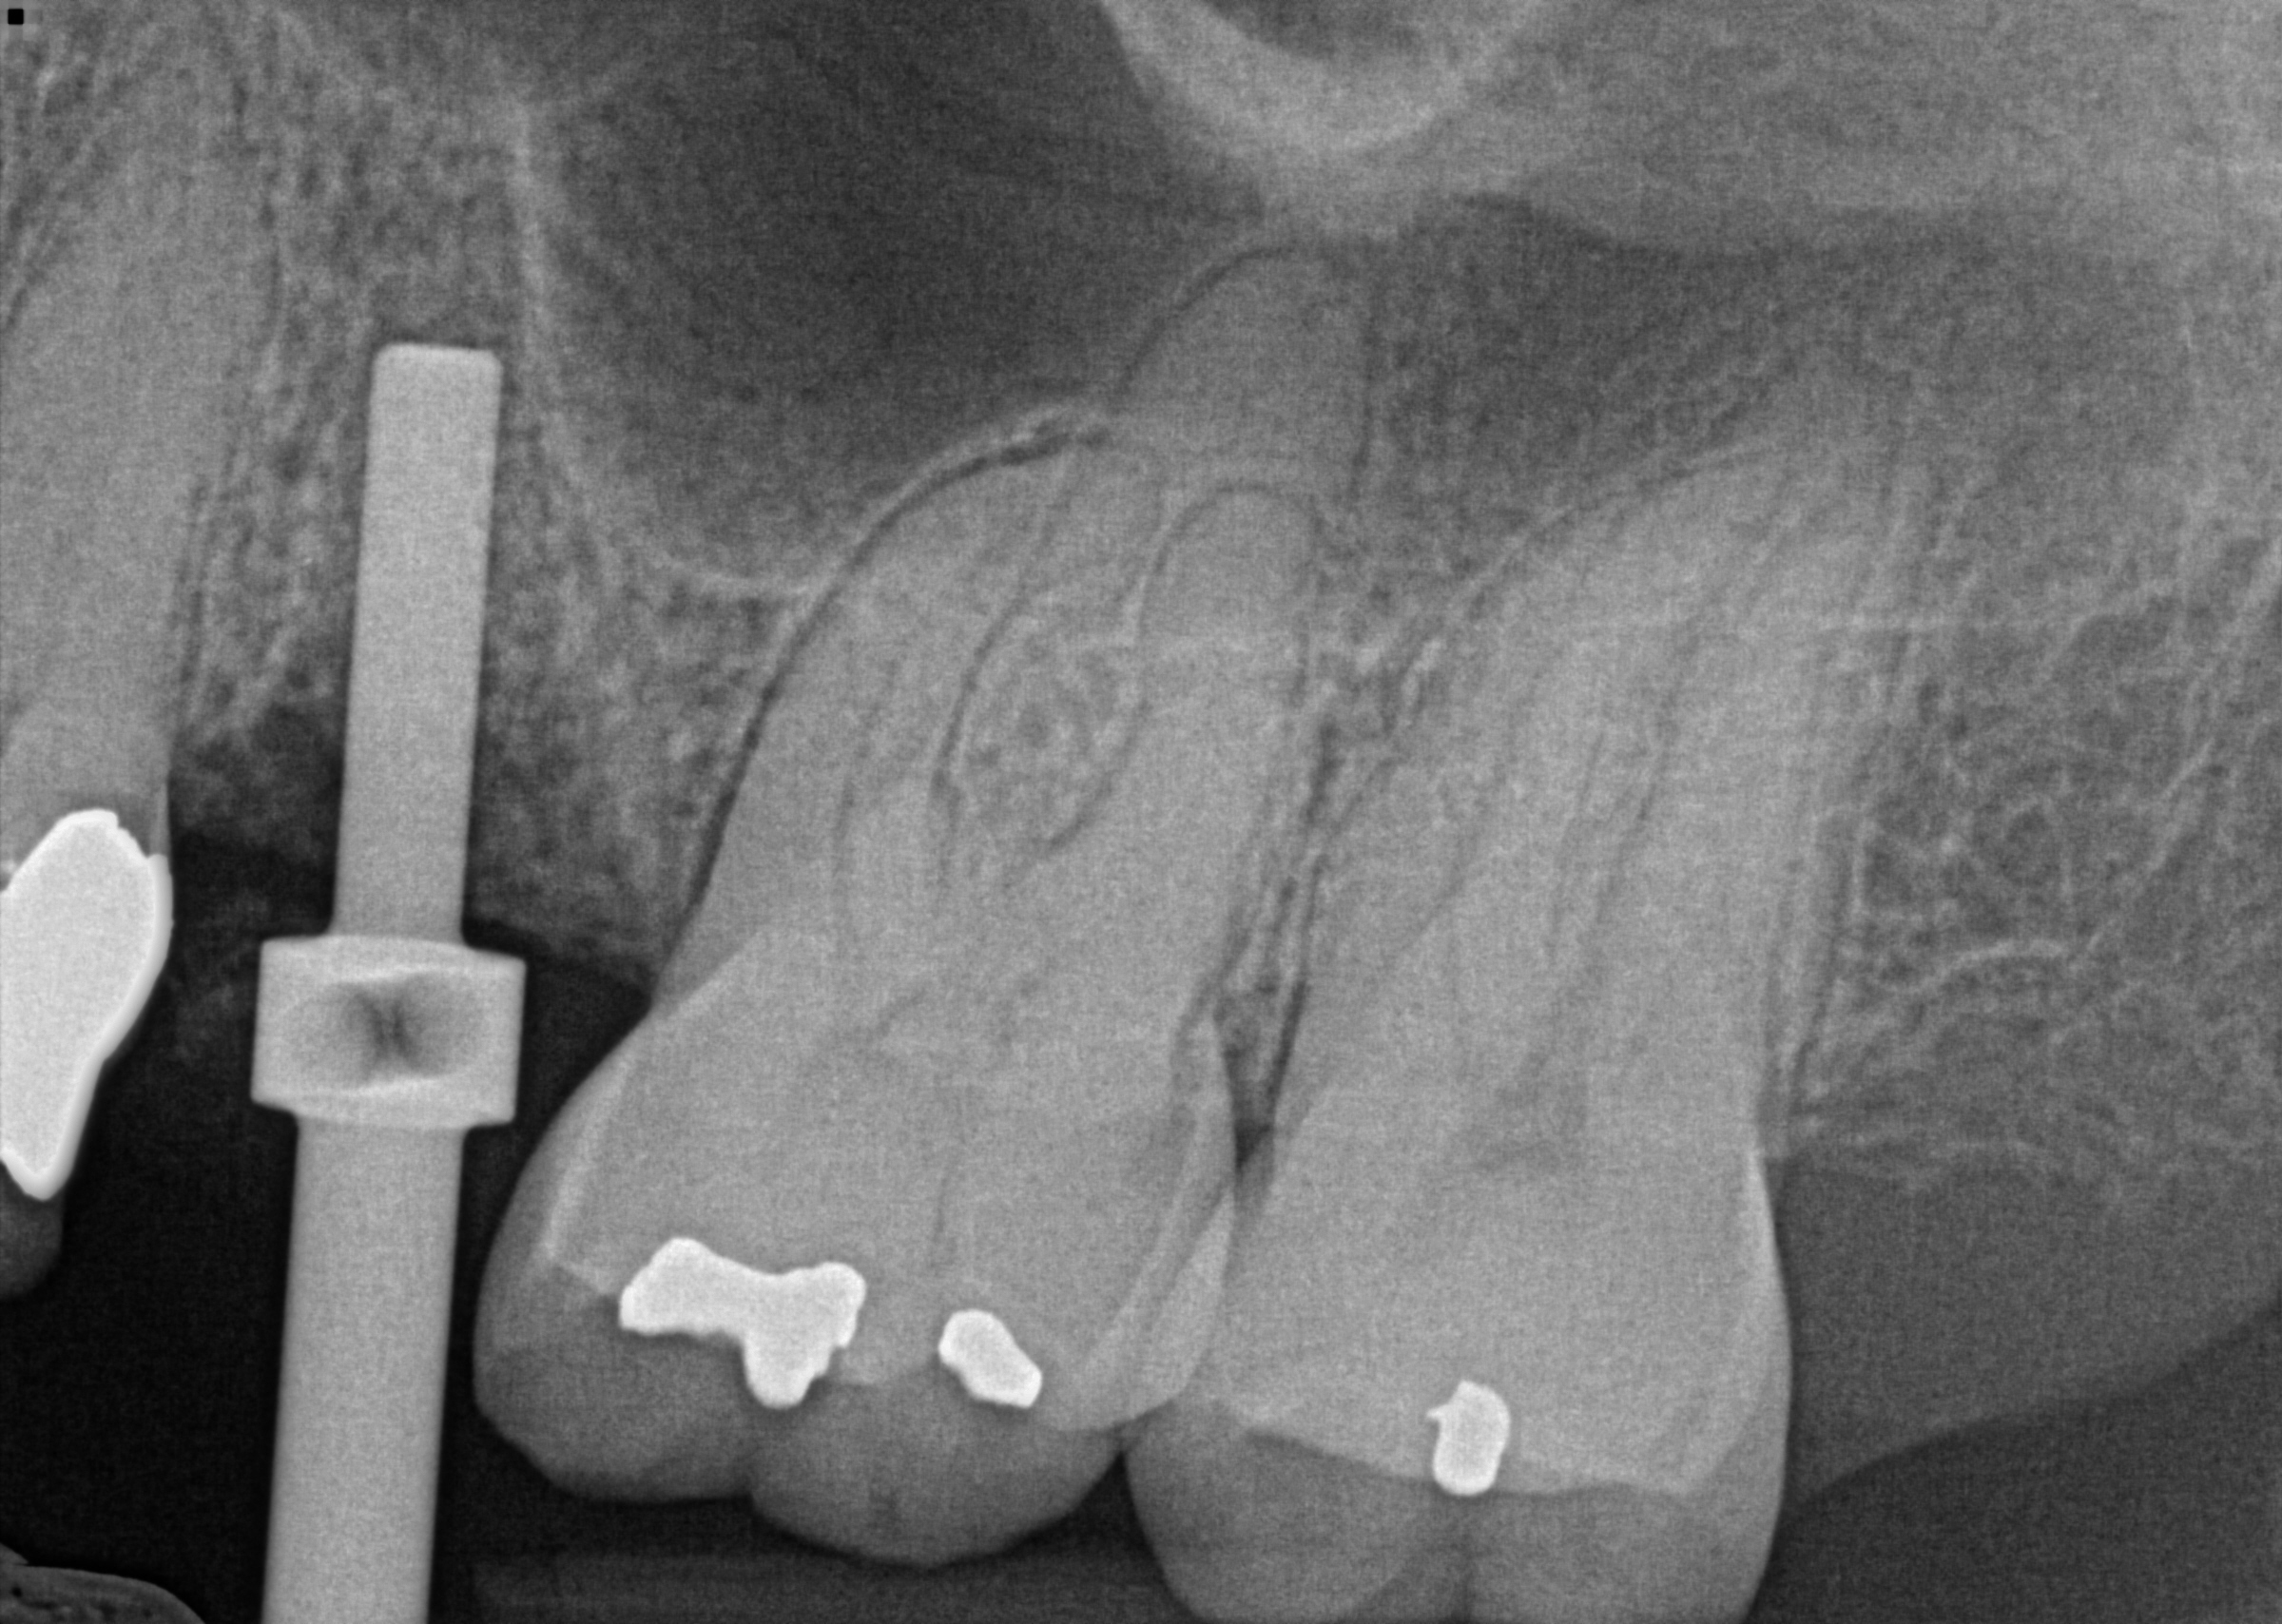

Sinus lift #13 case

This case required careful planning using advanced CBCT imaging, available at our Orland Park dental office. Tooth #13 split in half and required extraction. The decision was made to graft the site and restore the tooth with a dental implant. The 3d image showed a low sinus floor that required indirect sinus lifting, and careful insertion of the implant achieved that. The patient is now awaiting her crown after a 4 month period for healing. A guiding pin is shown in the first implant, followed by the insertion of the implant after the floor of the sinus was lifted.